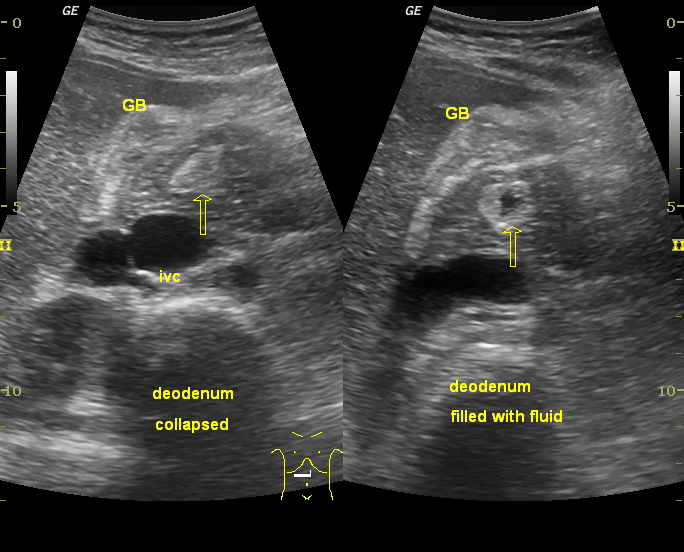

УЗИ диагностика кольцевидной поджелудочной железы: что важно знать